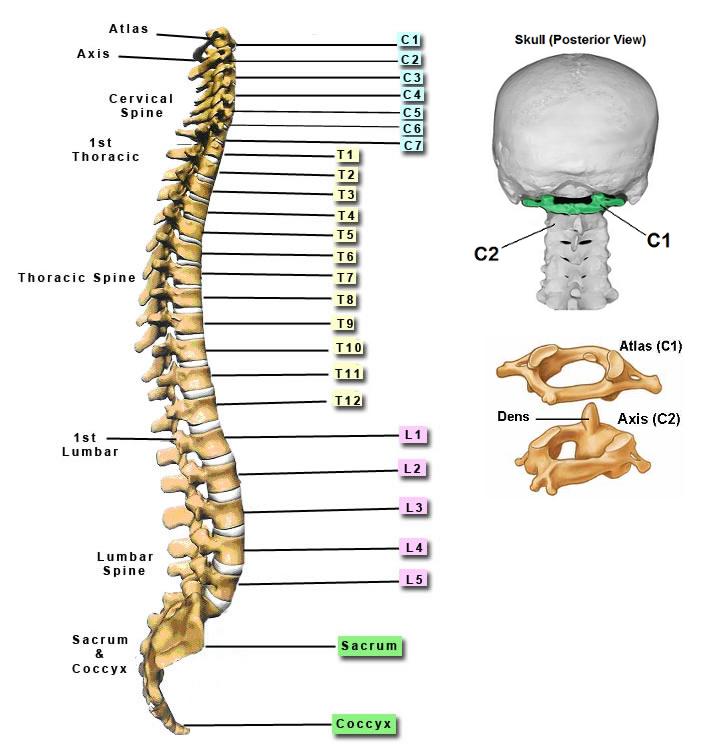

silikonsheet.blogg.se – Spine diagram

diagram of cervical and thoracic spine – Google Search | Spinal cord …

Anatomy of the Spine | Globus Medical

Anatomy of the Spine | Wessex Spinal Surgeon

The Cervical Spine: Anatomy, Function, and Common | Spine Center of …

Spine Anatomy and Back Pain – The Core Expert

Normal Cervical Spine Anatomy – TrialExhibits Inc.

Anatomy of the Cervical Spine – TrialExhibits Inc.